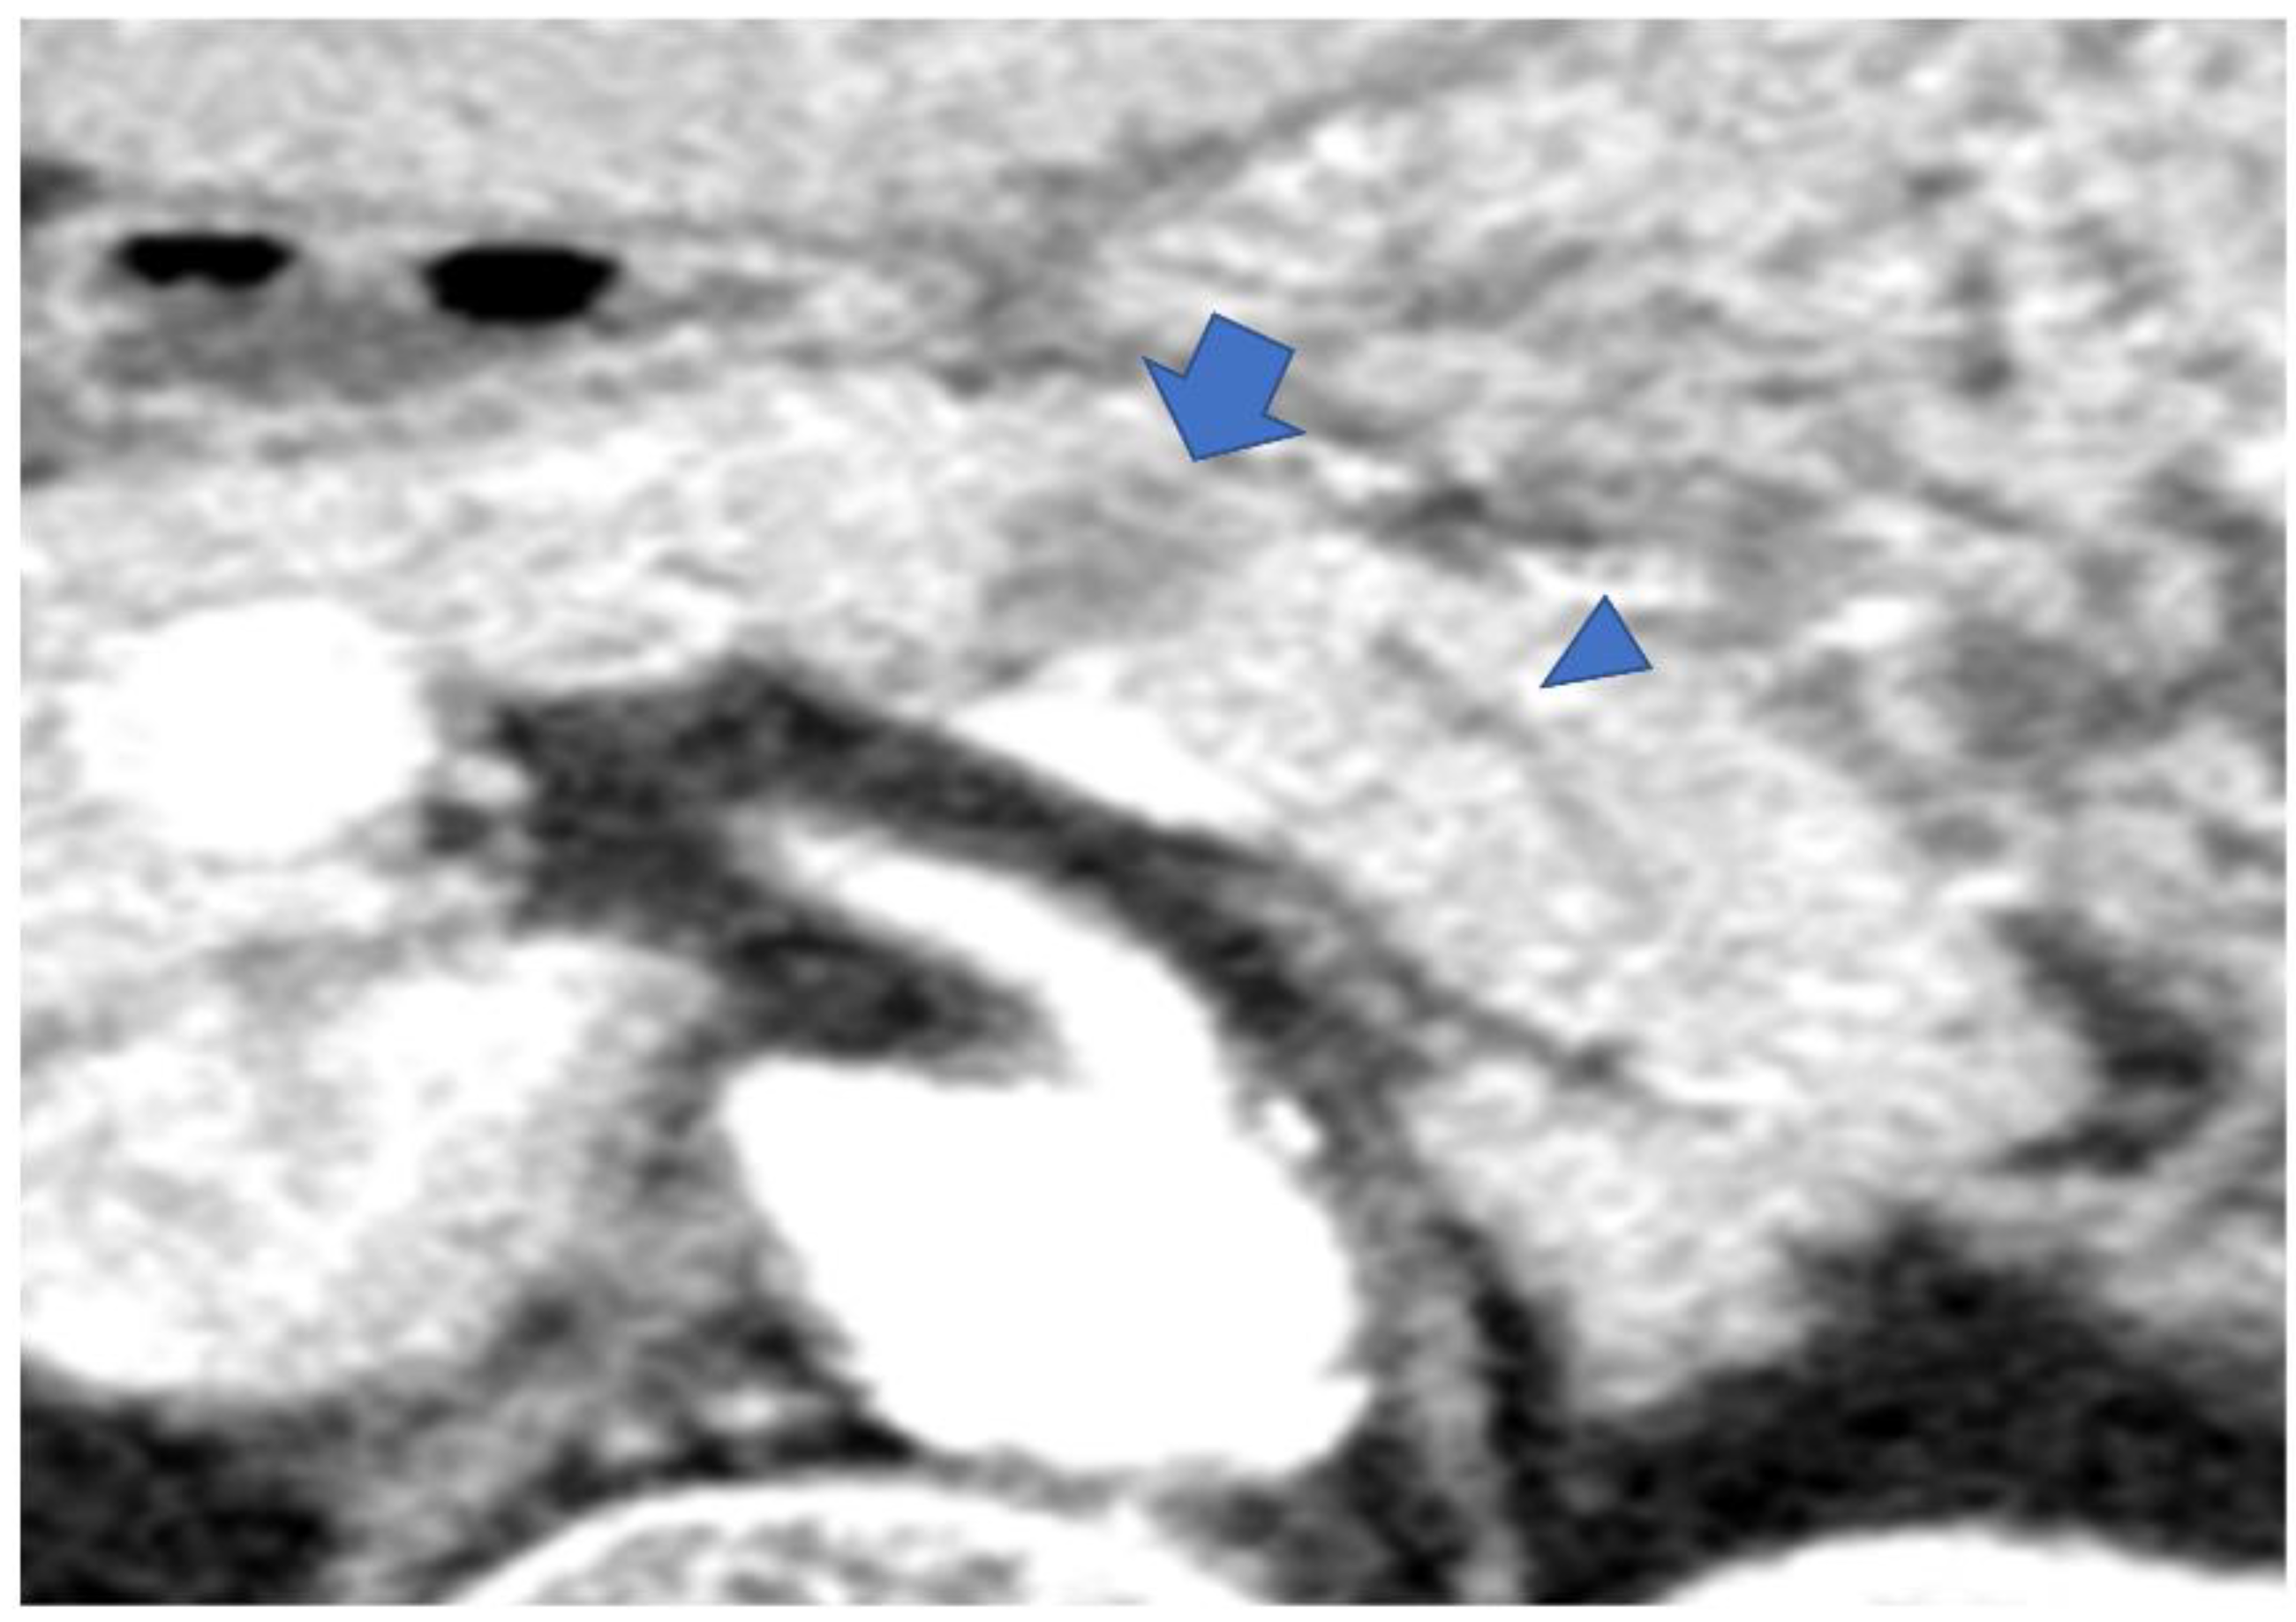

- Miura, S.; Takikawa, T.; Kikuta, K.; Hamada, S.; Kume, K.; Yoshida, N.; Tanaka, Y.; Matsumoto, R.; Ikeda, M.; Kataoka, F.; et al. Focal Parenchymal Atrophy of the Pancreas Is Frequently Observed on Pre-Diagnostic Computed Tomography in Patients with Pancreatic Cancer: A Case-Control Study. Diagnostics 2021, 11, 1693. [Google Scholar] [CrossRef] [PubMed]

- Nakahodo, J.; Kikuyama, M.; Nojiri, S.; Chiba, K.; Yoshimoto, K.; Kamisawa, T.; Horiguchi, S.I.; Honda, G. Focal parenchymal atrophy of pancreas: An important sign of underlying high-grade pancreatic intraepithelial neoplasia without invasive carcinoma, i.e., carcinoma in situ. Pancreatology 2020, 20, 1689–1697. [Google Scholar] [CrossRef] [PubMed]

- Miura, S.; Kume, K.; Kikuta, K.; Hamada, S.; Takikawa, T.; Yoshida, N.; Hongo, S.; Tanaka, Y.; Matsumoto, R.; Sano, T.; et al. Focal Parenchymal Atrophy and Fat Replacement Are Clues for Early Diagnosis of Pancreatic Cancer with Abnormalities of the Main Pancreatic Duct. Tohoku J. Exp. Med. 2020, 252, 63–71. [Google Scholar] [CrossRef]